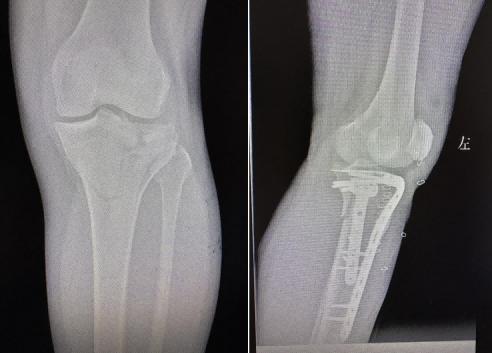

45岁的张先生因意外摔伤导致右膝关节疼痛肿胀,无法活动,经急诊检查确诊为胫骨平台骨折。胫骨平台作为膝关节的重要承重结构,骨折后若复位不佳,易引发关节畸形、创伤性关节炎等后遗症。传统手术需较大切口暴露骨折部位,不仅创伤大,还可能损伤膝关节周围软组织。创伤骨科团队结合患者影像学检查结果,采用微创复位内固定术。术中,医生通过小切口建立操作通道,在C型臂X光机精准引导下,将移位的骨折块复位,植入锁定钢板完成固定。手术顺利,目前该患者已康复出院。